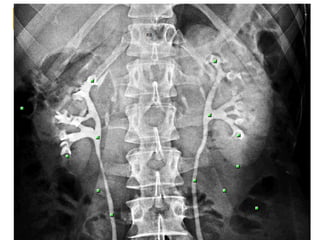

ANATOMIA DOS RINS

   Os rins são dois órgãos marrom-avermelhados

situados na parede posterior da cavidade

abdominal, um em cada lado da coluna vertebral.

   Os rins apresentam aproximadamente 11 cm de

comprimento e se estendem desde o nível da T11

ou T12 até a L3. Devido à presença do fígado, o rim

direito é ligeiramente inferior em relação ao rim

esquerdo.